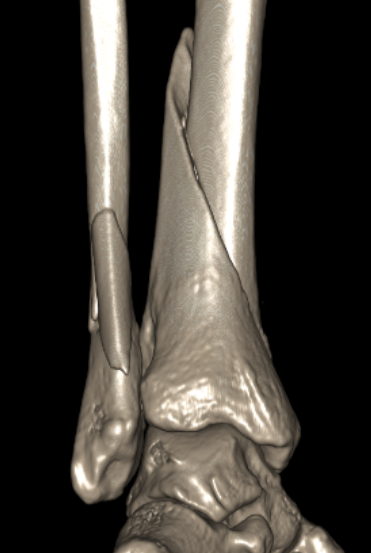

CT scan

Commonly 3 fracture configurations

- medial malleolus

- posterolateral fragment / Volkmann

- anterolateral fragment / Chaput